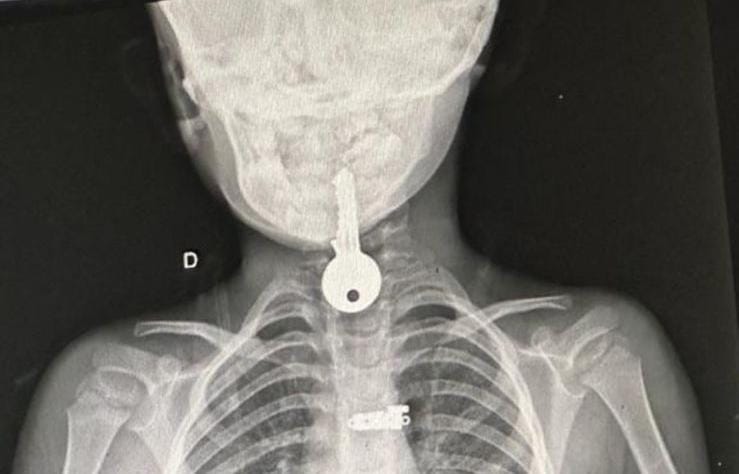

Na manhã desta segunda-feira, uma criança de 4 anos, do sexo masculino, proveniente do município de Porto Walter, foi encaminhada via TFD para a cidade de Cruzeiro do Sul devido a um incidente preocupante. A criança havia engolido uma chave que ficou presa em seu esôfago.

No final da tarde, ela chegou a Cruzeiro do Sul, onde foi prontamente atendida pelo cirurgião Dr. Marlon Holanda que realizou o procedimento por endoscopia com sucesso, retirando objeto do esôfago da criança.